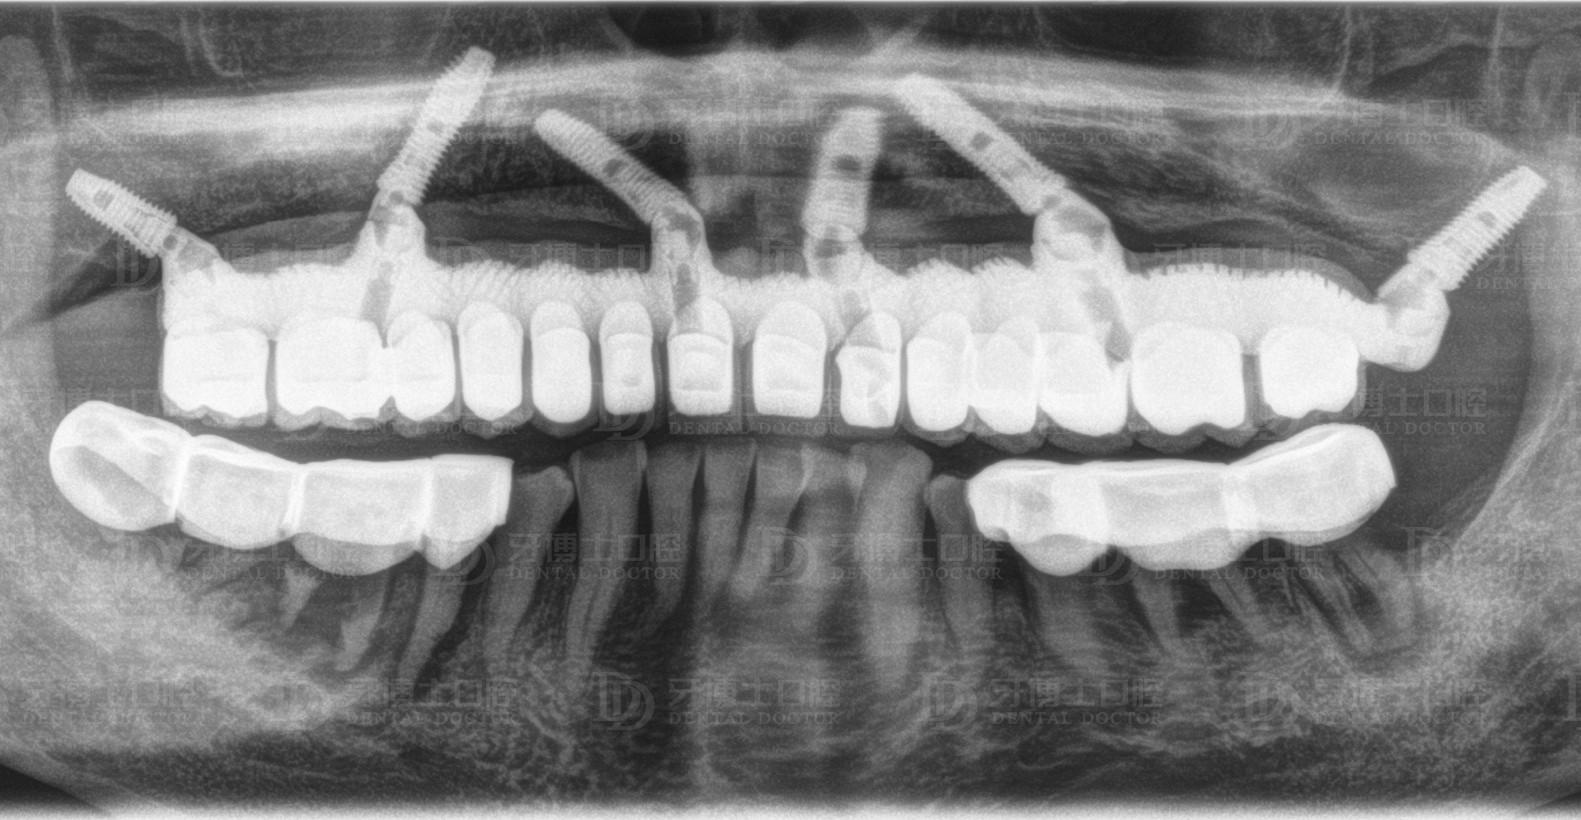

醫(yī)生根據(jù)他的骨量,設(shè)計(jì)了負(fù)重種植6顆恢復(fù)半口牙的方案,上午種牙,下午戴牙。種牙1個(gè)月后,精神狀態(tài)好,種牙3個(gè)月后,整個(gè)人圓了一圈,周老激動(dòng)地跟醫(yī)生說(shuō)了好些感謝的話,感慨老年生活從未這么順心過(guò)。

上半口種植6顆

All-on-4/6種植是一項(xiàng)高深精密的手術(shù),對(duì)醫(yī)生技術(shù)、醫(yī)療設(shè)備的要求嚴(yán)格。因?yàn)榉N植牙上午種,下午就得受力,所以醫(yī)生需要辨別骨頭的質(zhì)量、密度,種進(jìn)去的每一顆植體擁有35牛的扭力,如果植體很松,戴上牙冠后便會(huì)搖晃,就意味著種植失敗,這是種植技術(shù)的難點(diǎn)之一。